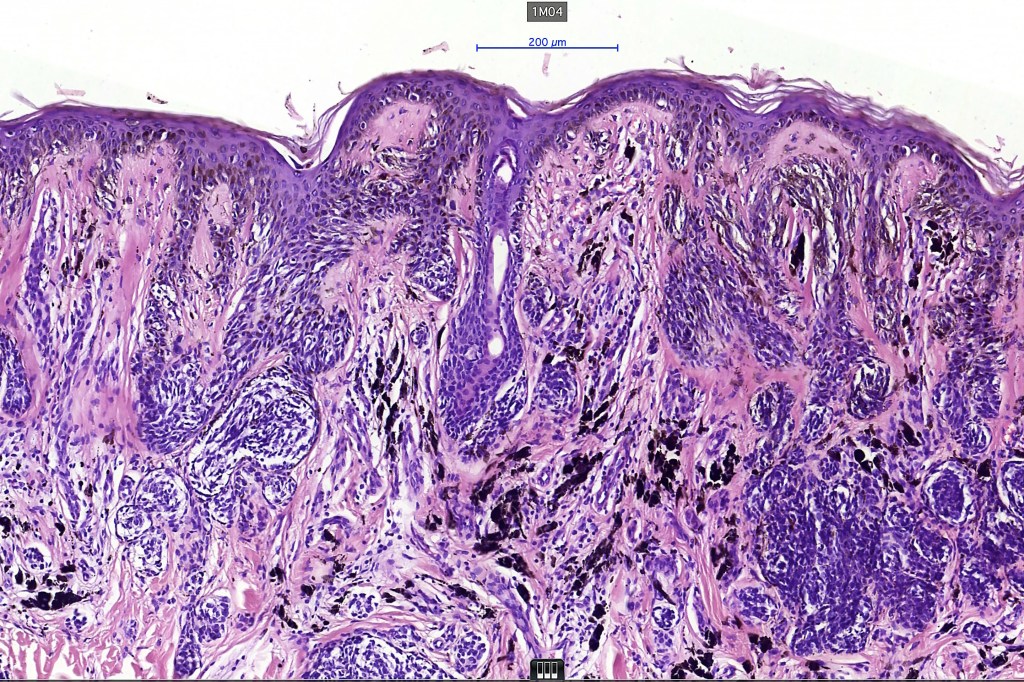

•In compound lesions, the nest size should be smaller than the junctional ones and the degree of atypia the same or less

Dysplastic nevus in the majority of cases is instantly recognizable, often at low power. The most important differential diagnosis is obviously melanoma. In junctional lesions, widespread/uniform high grade atypia, frequent mitoses and Pagetoid spread are indicative of in situ melanoma. In compound lesions, dermal nests larger than junctional ones, expansile dermal nests, severe atypia and mitotic activity indicate the presence of melanoma

Dysplastic nevus with early melanoma